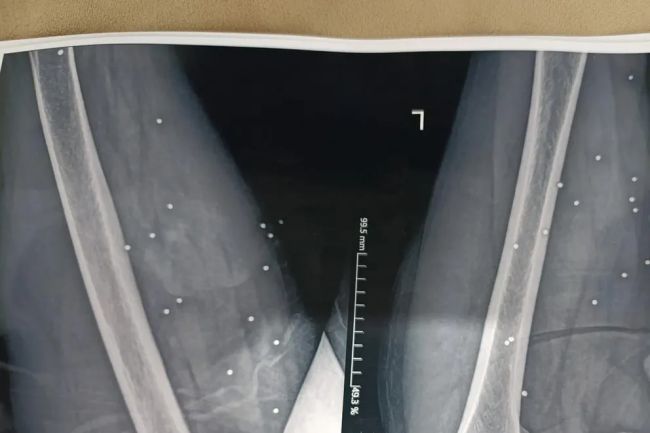

در یکی از تصاویر، نزدیک به ۲۰۰ ساچمه در ران و لگن یک زن میانسال دیده شده است.

تحلیل پزشکی نشان می‌دهد این نوع جراحات می‌تواند به آسیب شدید اندام‌های داخلی، بی‌اختیاری در کنترل ادرار، ناباروری و ناتوانی جنسی منجر شود.

این پیامدها در بسیاری از موارد، دائمی خواهند بود.گلوله‌های تمام‌فلزی